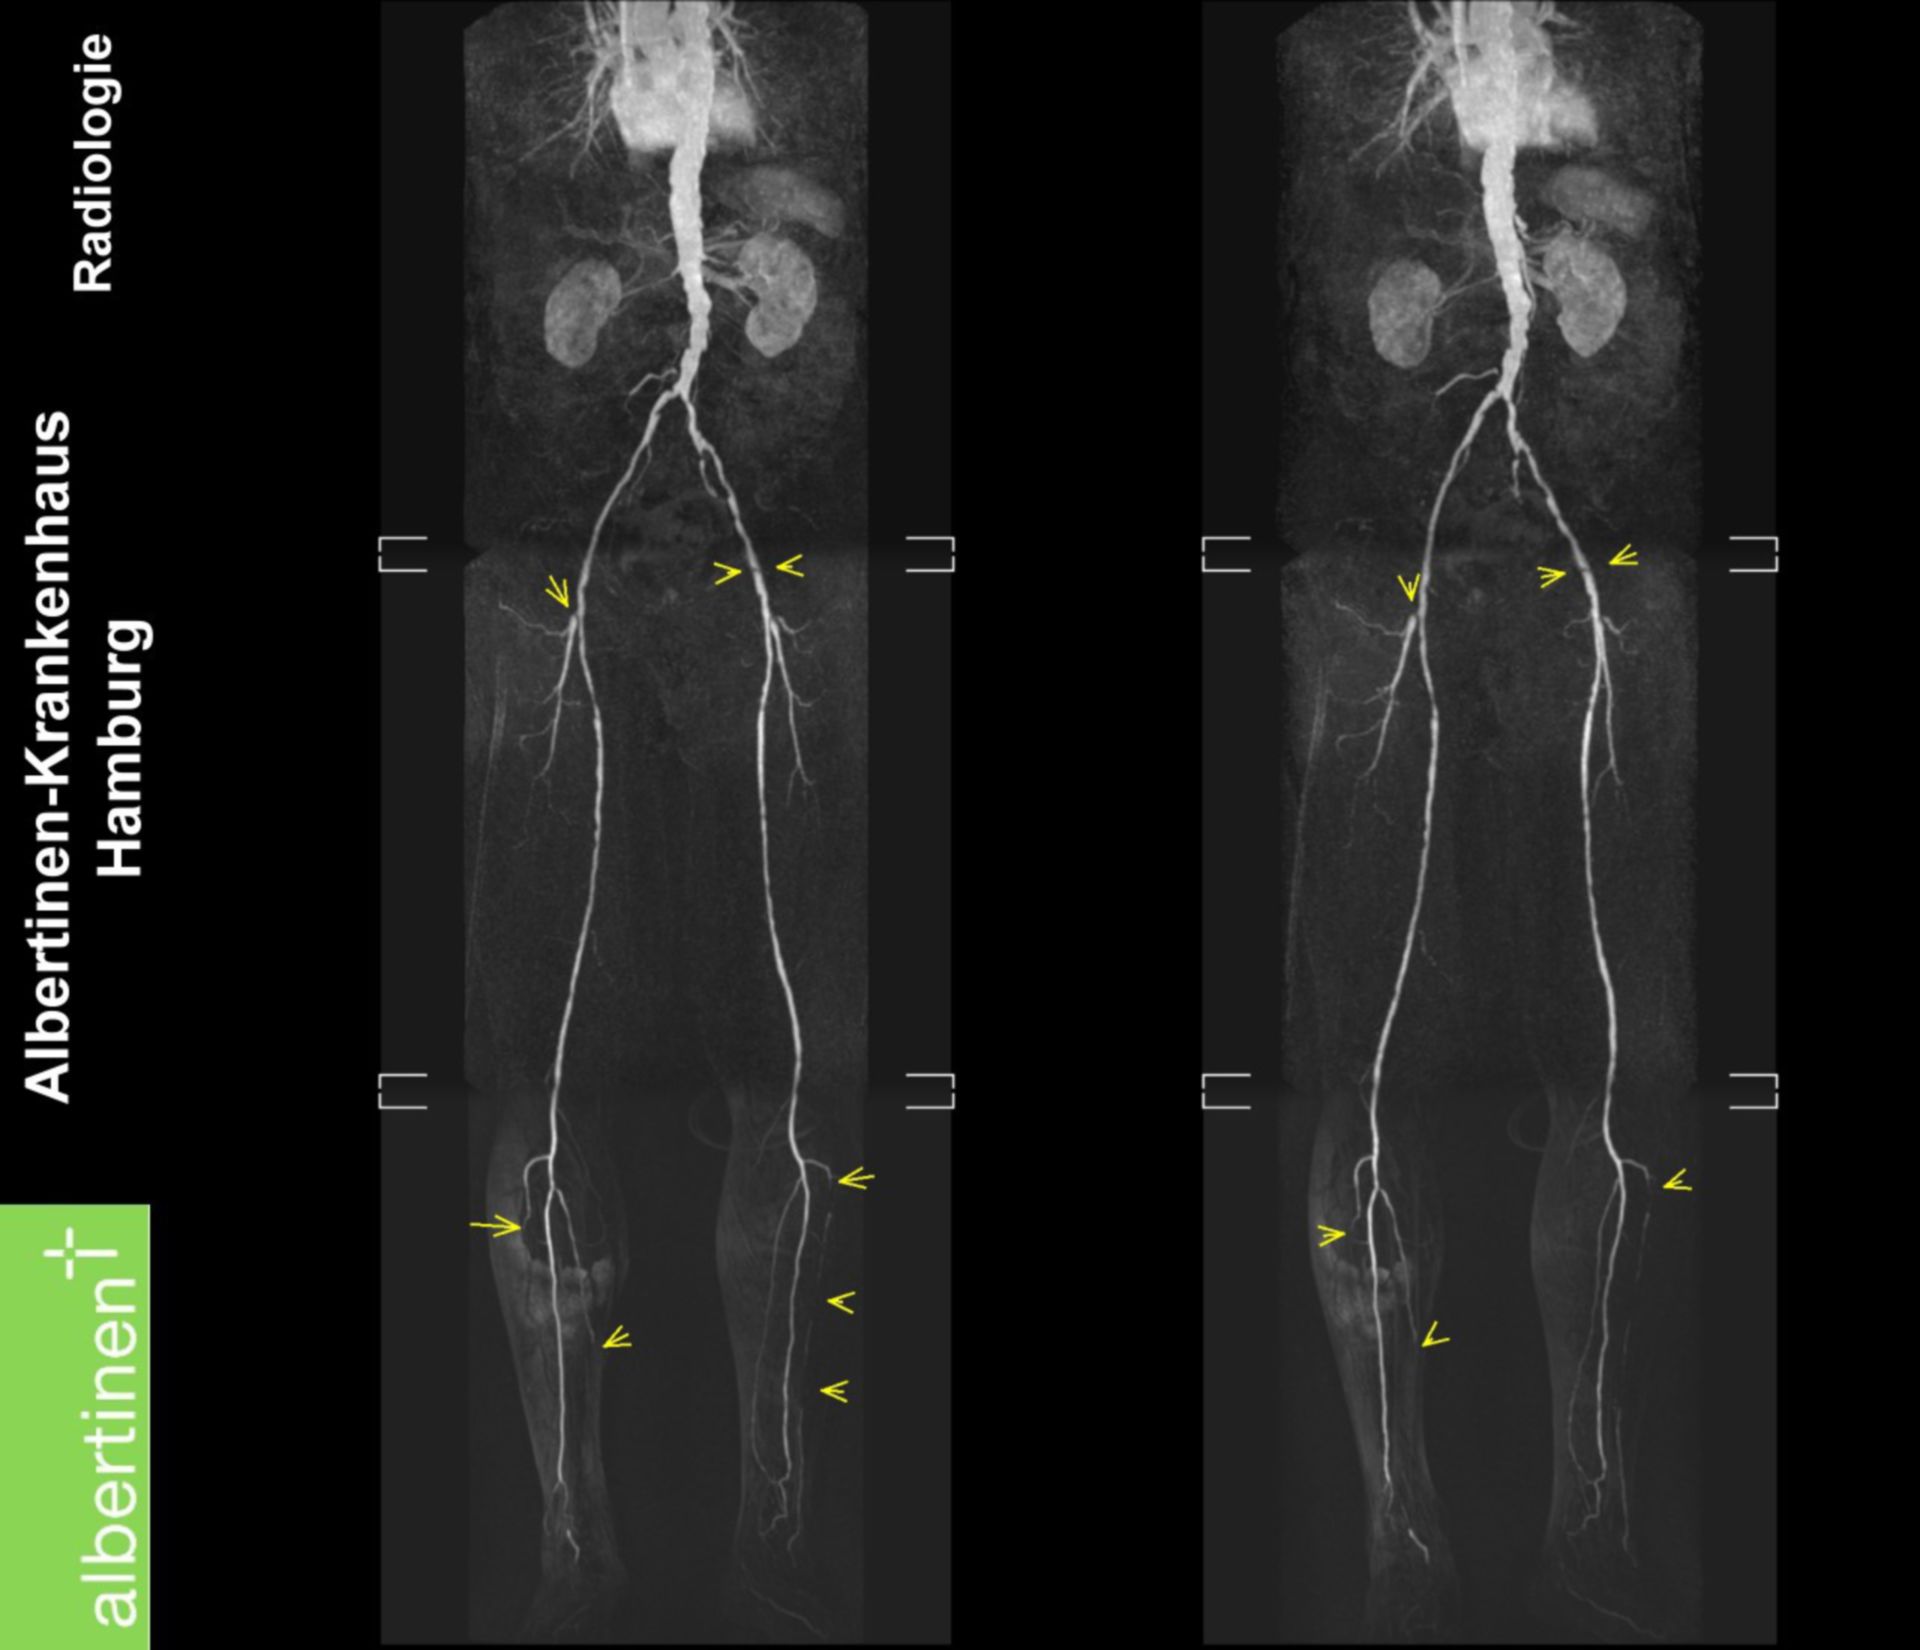

Mrt Circle Line Malaysia / The mrt 3, mrt line 3 or mrt circle line is a proposed thirteenth … MRT: AVK der Beinarterien – DocCheck

MRT: AVK der Beinarterien – DocCheck Magnetresonanztomographie (MRT) – Institut für Diagnostische und Interventionelle Radiologie …

MRT Übersichtsaufnahme – DocCheck MRT Schädel – DocCheck